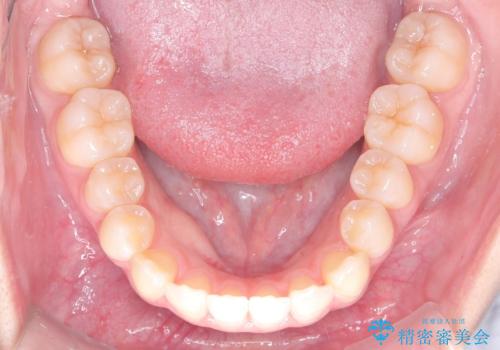

- 右上の小臼歯が大きくねじれており、噛み合わせや見た目に影響を与えている状態でした。診察の結果、インビザライン単独では十分な回転が得られにくいと判断。そのため、基本的な歯列の移動はインビザラインで行いながら、部分的にワイヤー矯正を併用するコンビネーション治療を計画しました。

まず、インビザラインで歯列全体を整えながら、スペースを確保しました。その後、部分ワイヤーを装着し、右上小臼歯の捻転を効率よく改善。ワイヤーの力を活用することで、より確実に歯の向きを整えることができました。治療後は、「しっかり噛めるようになり、見た目も自然になった」と患者様にもご満足いただきました。